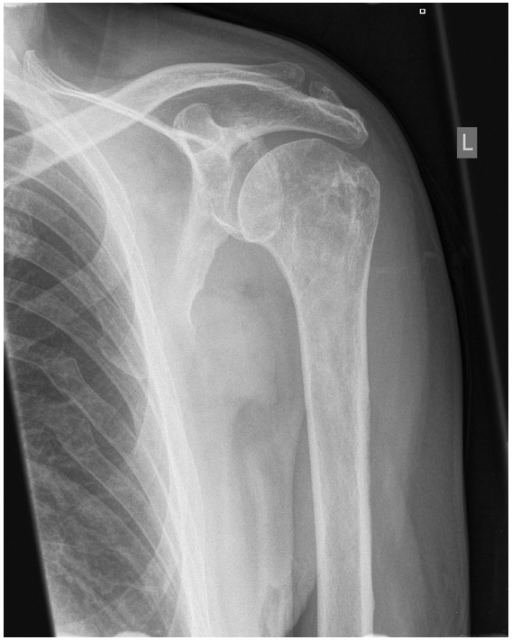

Shoulder Pathologies – Musculoskeletal Portfolio

Radiograph of the left shoulder, AP view: a rounded lytic lesion is …

Anteroposterior X-ray of the patient’s right shoulder demonstrating …

X-rays of the left shoulder revelead a bony mass arising from the …

Shoulder Osteoarthritis Presentation and Treatment | Bone and Spine

Shoulder fractures; Humeral Fractures, Proximal